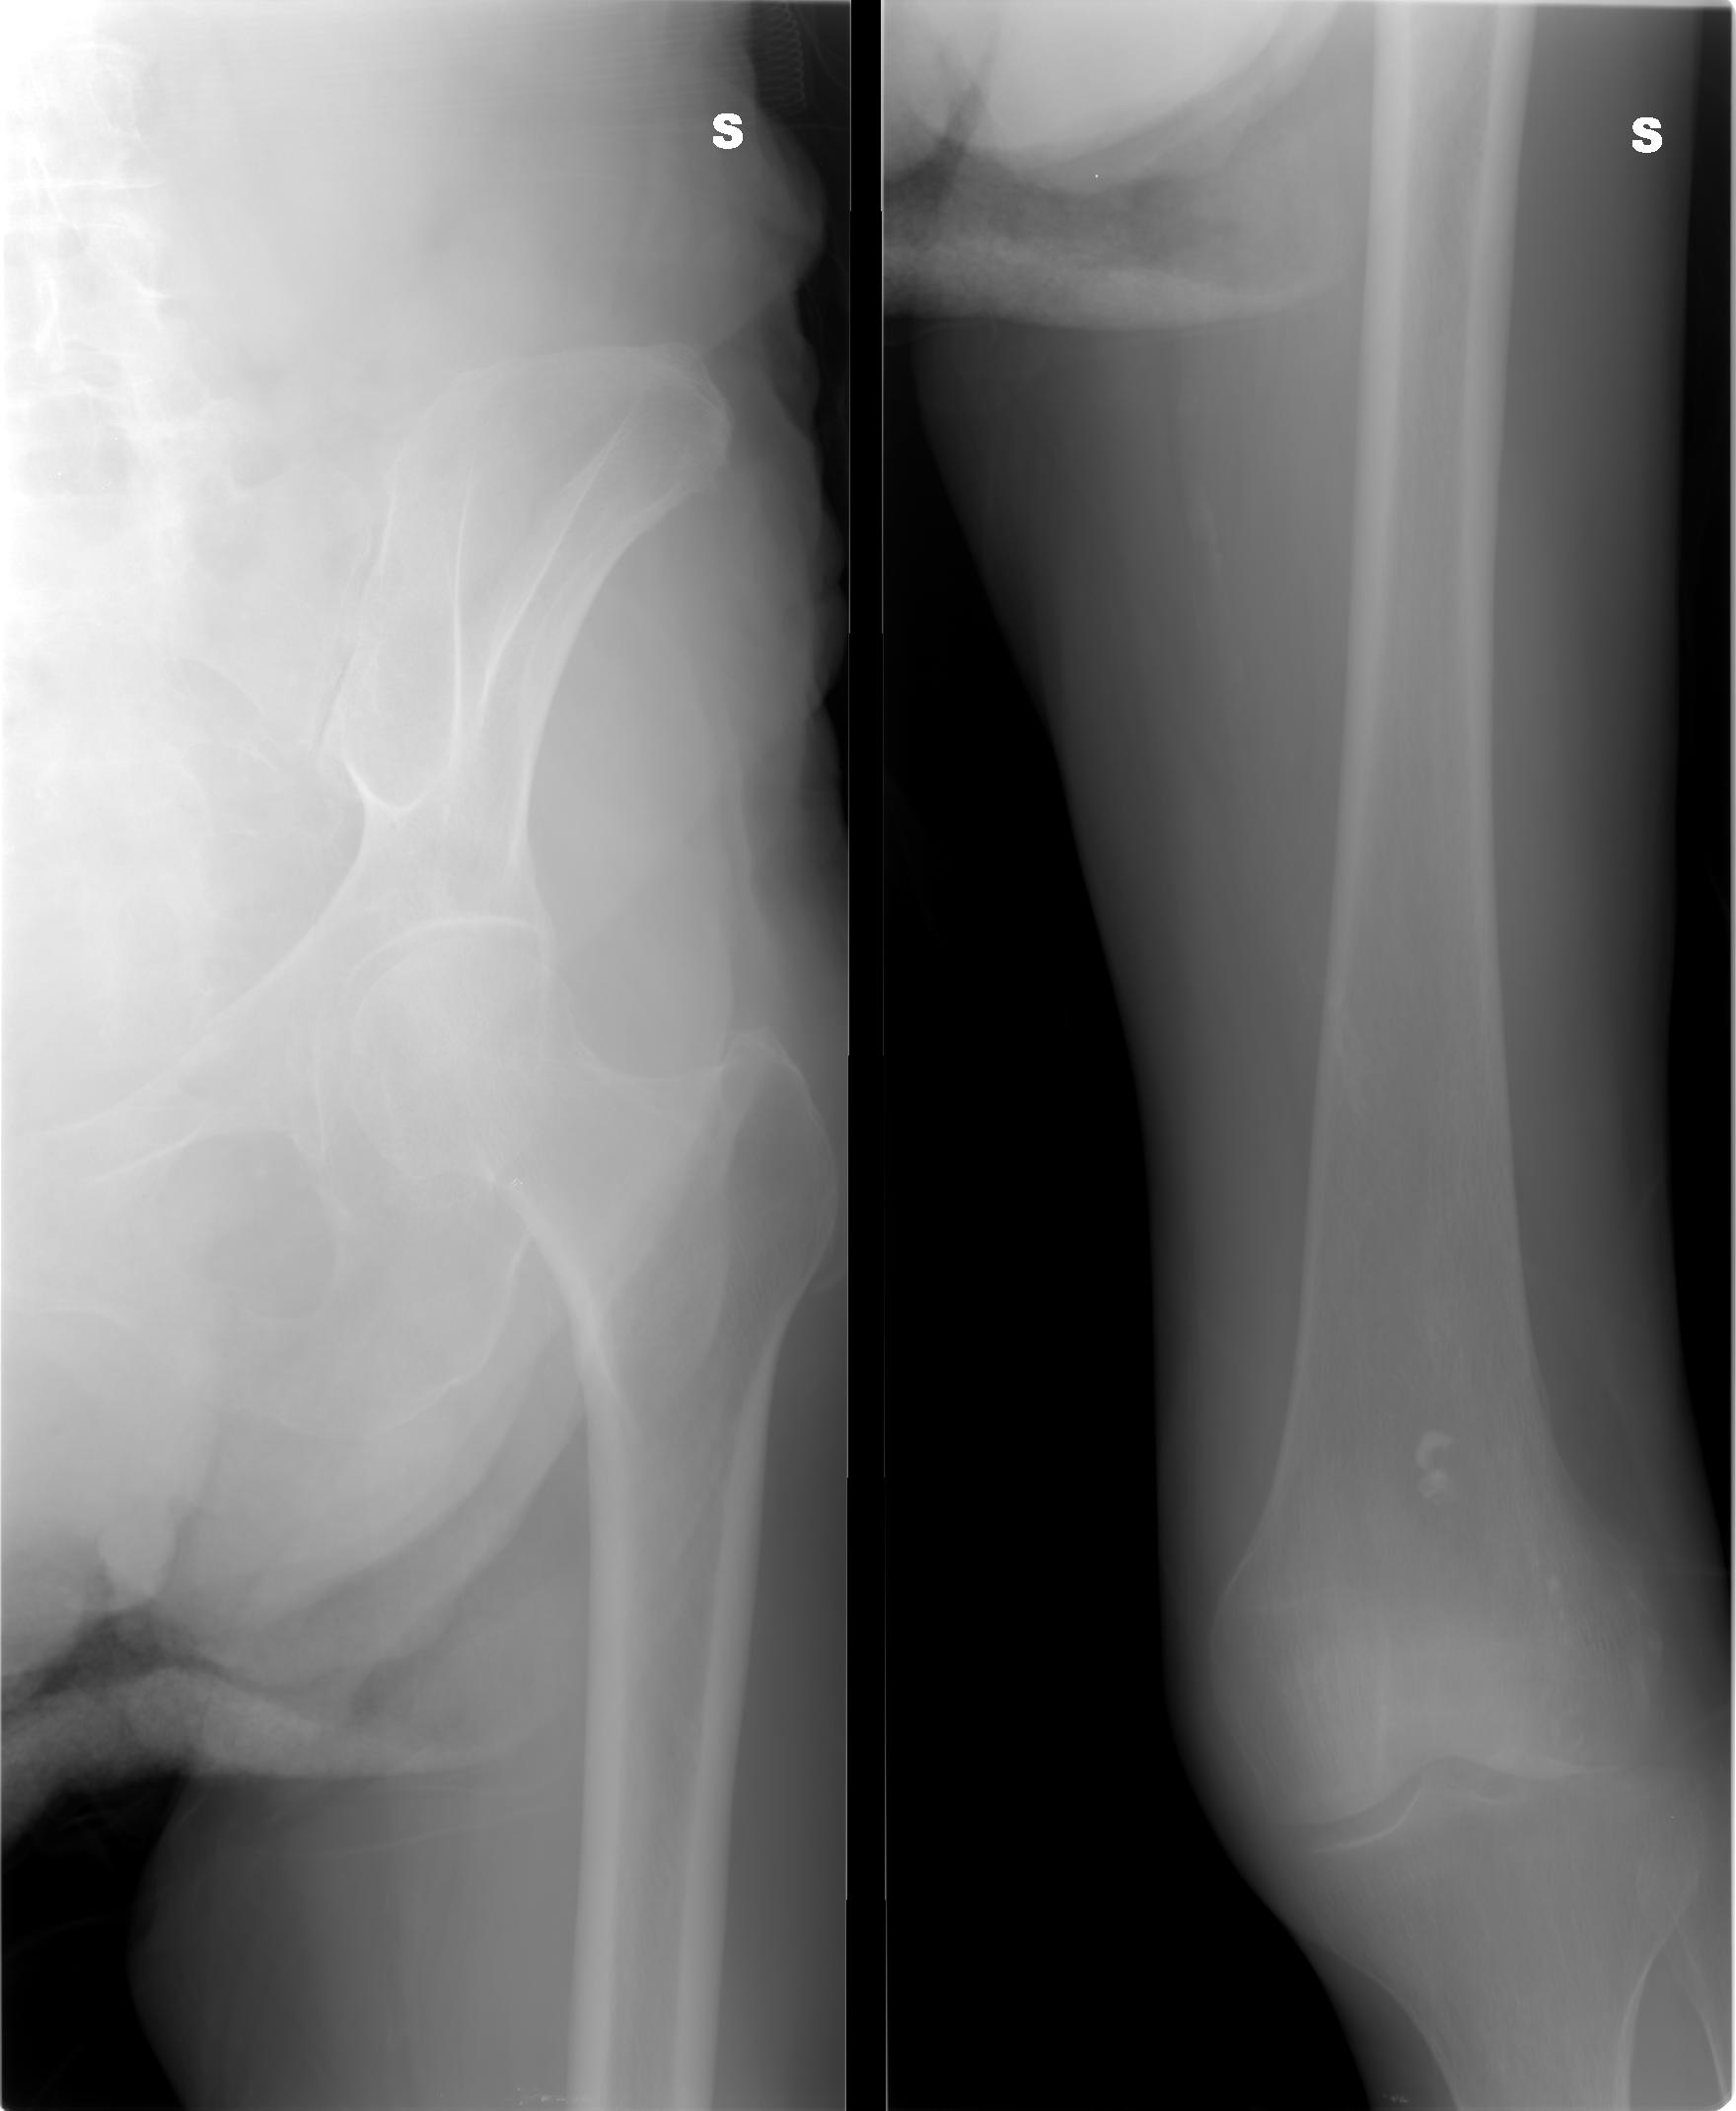

SALVE, ho ritirato un referto lastra per mia madre 80 anni e dice le seguenti parole: per quanto apprezzabile nel radiogramma a disposizione si osserva frattura composta della branca ile pubica sinistra .Sospetta frattura (o esiti fratturativi?) a carico dell branca ischio pubica omolaterale.

allego le lastre potete consigliarmi?

I00001 (2).JPG

[ 113.6 KiB | Osservato 1195 volte ]